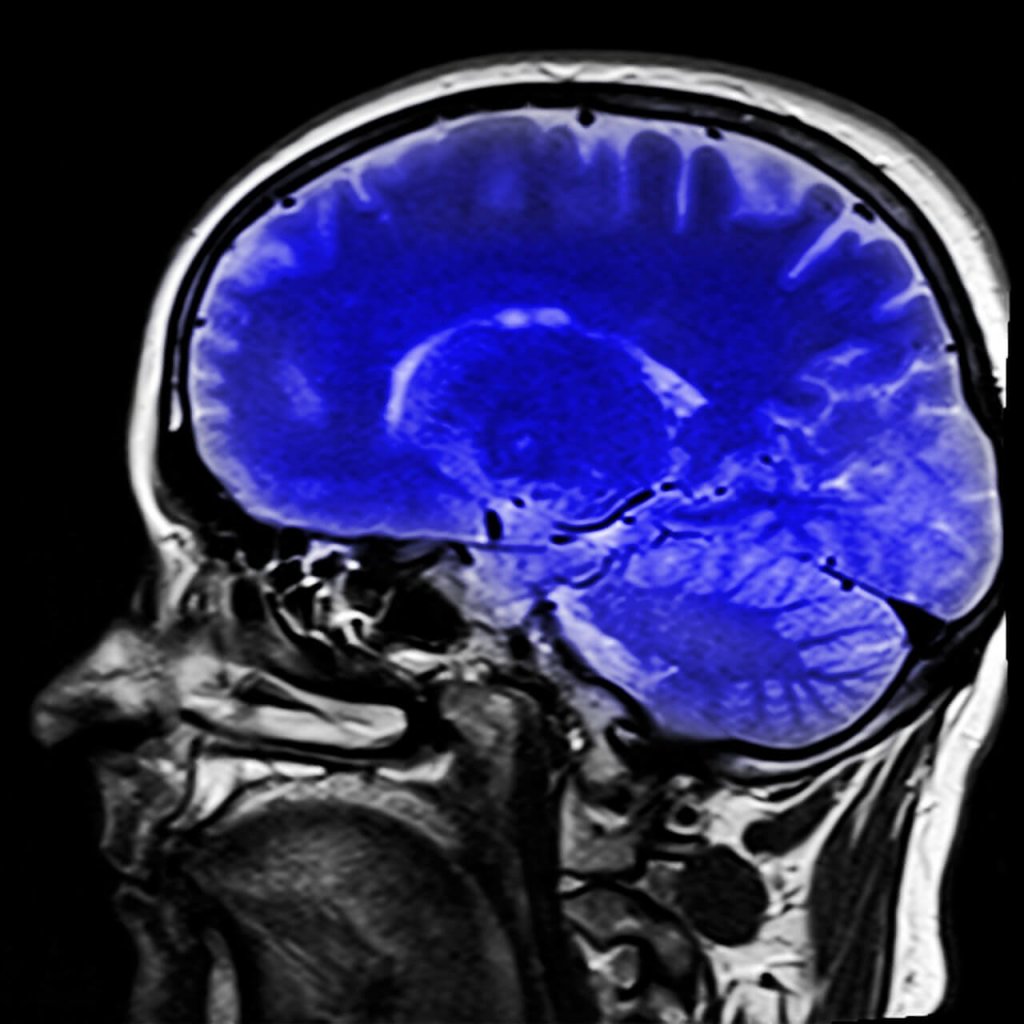

Esistono, però, alcune prove neurologiche che aiutano la diagnosi. La risonanza magnetica può mostrare il tipo di lesione cerebrale grazie alla quale è possibile orientarsi o meno verso questa sindrome.